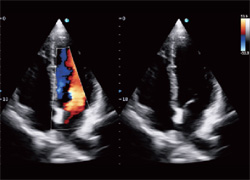

Примеры изображений: